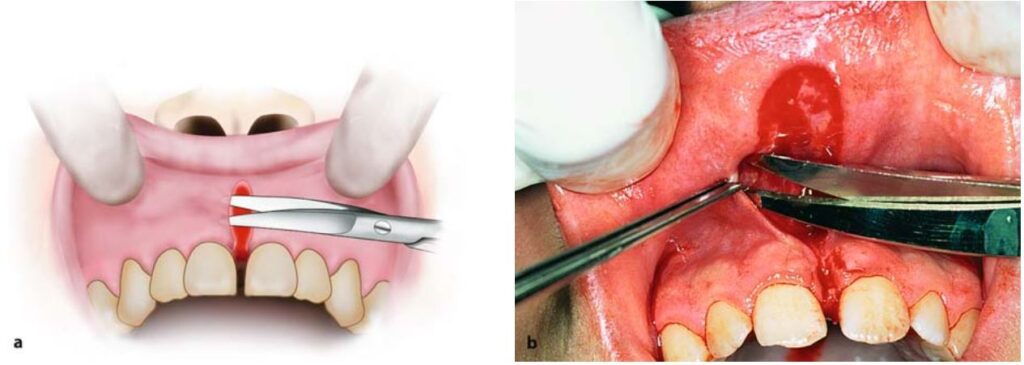

Nếu thắng môi quá dày và có khe hở quá rộng giữa 2 răng cửa thì thường cắt bỏ luôn phần mô mềm ở giữa và sau 2 răng cửa này (H10.79).

Thực hiện khâu vết thương sau khi đã dùng kéo để làm giảm căng mô quanh bờ tổn thương (H10.80 – 10.82).